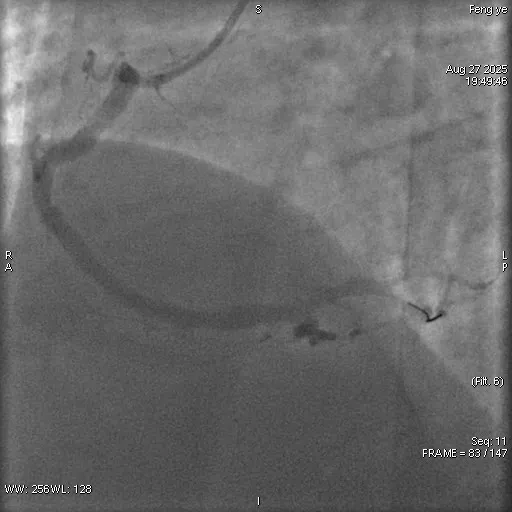

术前

术后

紧急救治:介入手术打通血管,从死亡线拉回生命

抵达四院急诊室时,张先生的病情已十分危急。医护人员早已备好除颤仪以防万一,同时迅速为其完善心电图、心肌酶谱等关键检查。检查结果显示,张先生患上的是急性下壁正后壁心肌梗死—— 这是一种发病急、致死率高的心血管急症,若不及时干预,随时可能致命。

接到紧急会诊通知的四院心内科主任刘永生,第一时间赶到急诊室。结合张先生 “长期吸烟、高血压、高血糖、肥胖” 的病史与检查结果,刘永生判断其冠状动脉已出现急性闭塞,必须立即通过介入手术开通血管,否则将错失抢救时机。

随后,张先生被快速转运至导管室。刘永生带领团队精准定位其心脏冠状动脉闭塞部位,成功植入支架,打通了堵塞的血管。经过紧张抢救,张先生的生命体征逐渐平稳,胸闷、胸痛等症状明显缓解,最终脱离生命危险。目前,他已康复出院,出院后不仅彻底戒掉了多年烟瘾,还主动制定健康饮食与减重计划,积极配合后续康复治疗。